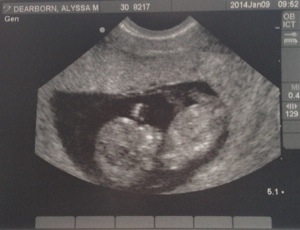

A week after we got home from Colorado we went to our first ultrasound on my birthday! Anyone who knows me knows how much I hate birthdays but this birthday in no way was like any of the others! The second that baby popped up on the screen I was in love! All my fears and anxieties were erased and I was left with the most overwhelming sense of pride and love! Baby was dancing all around so the doctor had a hard time even getting all the pictures she needed because baby was so active. Scott was so cute he was completely blown away by our baby exclaiming all sorts of things like “WOAH! There’s it’s foot” “This is so cool” “Haha, look at baby kicking you!” It was such fun for both of us! We just held hands and soaked in this wonderful moment. The heartbeat was very strong and the doctor put me in the LOW RISK PREGNANCY category! I don’t think there has ever been such music to my ears! Everything looked just as it should and with that all my fears were gone and I finally gave myself permission to jump into that pool of bliss!!